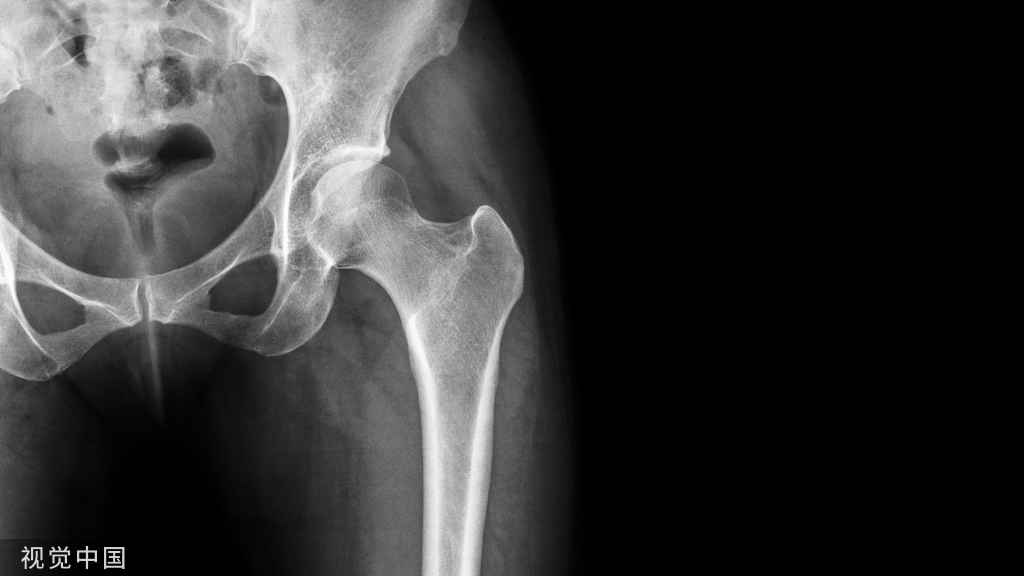

平片表现

- 骨皮质扇形凹陷

- 硬化边

- 致密性骨膜反应,尤其是在病灶近端、远端

- 病灶远端、近端骨皮质杯状改变

- 基质钙化(75%)

- 软组织肿块